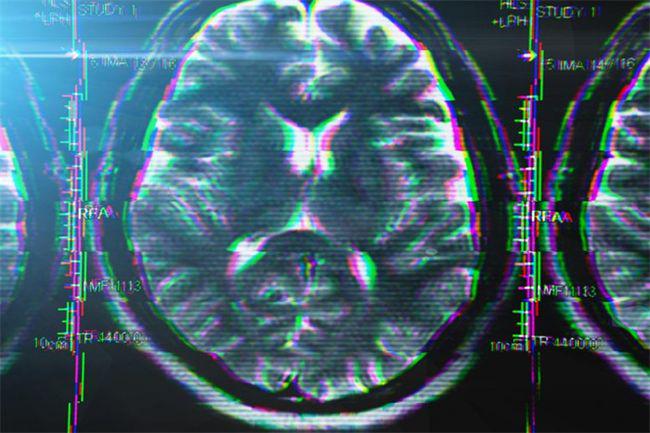

尤其需要大家注意的是,随着年龄的增长,大脑组织会渐渐萎缩,这种脑组织正常的体积缩小,虽然是自然老化的现象,但若经常出现记忆力下降、注意力不集中、精神心理异常、判断能力下降等等,就要当心了,或是病理性的表现,还可能影响一个人的寿命。